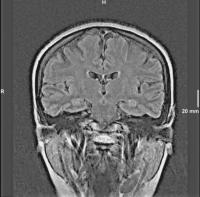

Abbildung 2: Die liquorsignalunterdrückte TIRM-Sequenz des Gehirns zeigt ein unauffälliges Signalverhalten der Hippokampusregion beidseits.

Keywords: GehirnHippokampusMRTTIRM-Sequenz